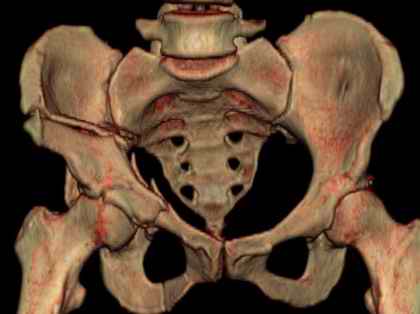

Посылаю схемы и 3D реконструкцию подобного повреждения. Называется он полным высоким двухколонным переломом вертлужной впадины, а "переломы крыла и тела подвздошной кости" входят в это понятие.

Вариантов остеосинтеза много (можно и не оперировть, т.к. конгруентность при таких переломах как правило сохраняется)

прикладываю схему доступа и случай.